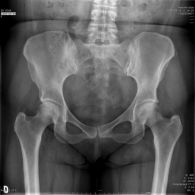

- Le Descellement signifie que la prothèse "ne tient plus dans l'os". Il peut survenir au niveau du fémur, du bassin ou les deux. Le descellement peut être secondaire à une infection (descellement septique) ou peut être mécanique (descellement aseptique). Le diagnostic est fait grace aux radiographies de hanche mais d'autres examens sont également à réaliser pour éliminer l'infection comme un bilan sanguin, une scintigraphie osseuse et une ponction de la hanche avec examen bactériologique du liquide articulaire.

- Le couple de frottement Métal-Métal de grand diamètre a été utilisé initialement devant un risque trés faible de luxation de PTH et d'usure des implants. Les défenseurs de ces prothèses les voyaient comme parfaites. Seulement, des débris d'usure métalliques sont créés suite aux mouvements de la prothèse et ces débris peuvent être à l'origine de douleurs, de réactions inflammatoires importantes et d'une destruction des tissus péri-articulaires (os, tendons, muscles...) Les patients porteurs d'une telle prothèse doivent être suivis de manière rapprochée par un chirurgien orthopédiste (même en cas d'absence de douleur). La surveillance consiste en des radiographies de la hanche régulières (tous les deux ans) et un dosage sanguin des ions métalliques à renouveler ou non en fonction des résultats et de la présence d'une symptomatologie douteuse.